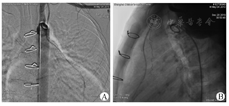

6例患儿术后随访9~22个月,所有患儿最近一次复查心电图结果显示ST段情况较术前明显改善。心脏彩色超声结果显示患儿术后冠状动脉血流通畅,无再狭窄发生,扩张段冠状动脉最大内径由术前(8.7±4.0)mm缩小至术后(6.4±2.3)mm(P<0.05);左心室射血分数由术前(55.7±10.3)%提高至术后(60.0±8.4)%(P>0.05)。2例患儿术后半年复查心导管造影显示桥血管远端冠状动脉血流TIMI分级Ⅲ级(图2)。6例患儿心功能恢复良好,纽约心脏协会(New York Heart Association,NYHA)心功能评级Ⅱ级以上,活动耐量均有明显增加,无胸闷晕厥等症状再发生。